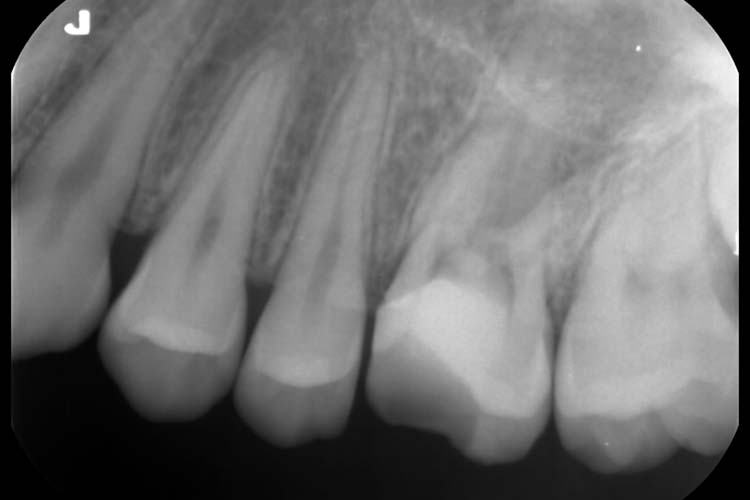

症例1

BEFORE

PROGRESS

AFTER

| 主訴 | 左上奥歯に違和感がある。 |

|---|---|

| 治療期間 | 5~6回 |

| 治療費 | 保険診療 |

| 治療内容 | 左上6番近心根に破折ファイルがあり、マイクロスコープ下で除去し、再根管治療を行った。 |

| 治療のリスク | 根管治療後、一時的に歯の根に痛みや違和感が生じることがあります。 |